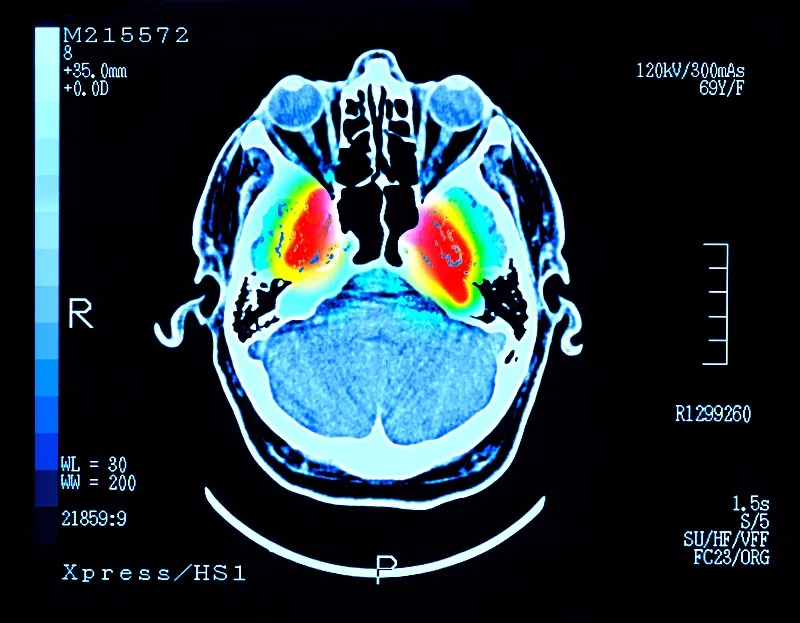

帕金森病 (PD) 是大腦中的一種疾病,它會(huì )殺死產(chǎn)生一種叫做“多巴胺”的化學(xué)物質(zhì)的神經(jīng)元。多巴胺是一種重要的化學(xué)物質(zhì),負責大腦內神經(jīng)元之間的交流。細胞死亡主要發(fā)生在“黑質(zhì)”,這是大腦中主要的多巴胺產(chǎn)生區域。

這些治療可緩解帕金森病的癥狀,但不會(huì )減緩或逆轉大腦神經(jīng)細胞的損傷。隨著(zhù)時(shí)間的推移,盡管進(jìn)行了治療,但臨床特征會(huì )變得更糟。當患者被診斷出患有帕金森癥時(shí),他們通常已經(jīng)患病多年,并且黑質(zhì)內的多巴胺細胞已經(jīng)丟失了一半以上。早期檢測帕金森癥的測試可能有所幫助,但科學(xué)家們正在尋找一種方法來(lái)替換受損的細胞。